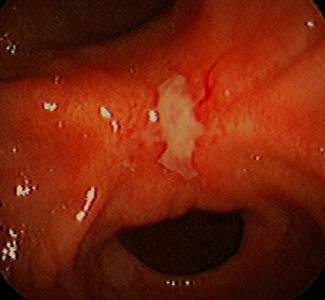

Voici à quoi ressemble une endoscopie pour ulcères gastriques chez le chien en vidéo (si vous n'êtes pas obligé de la regarder et que vous êtes facilement sensible, ne la regardez pas).